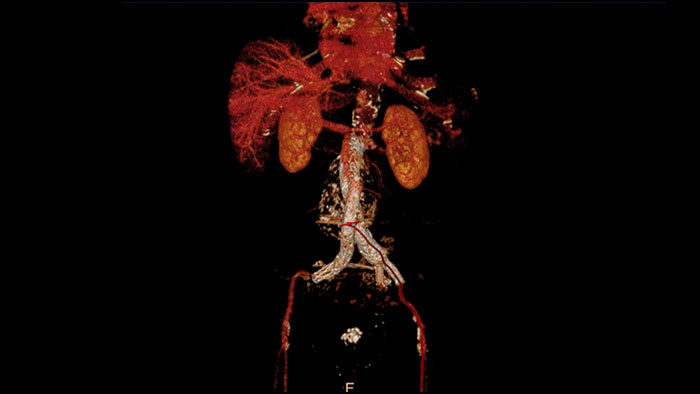

CT Spectral Advanced Vessel Analysis

IQon Spectral CT Functionality

Benefits

- Bone removal on different energy levels.

- Spectral plots to characterize plaque and stenosis.

- Different energy results comparison.

- Evaluation of the extent of lumen occlusion.